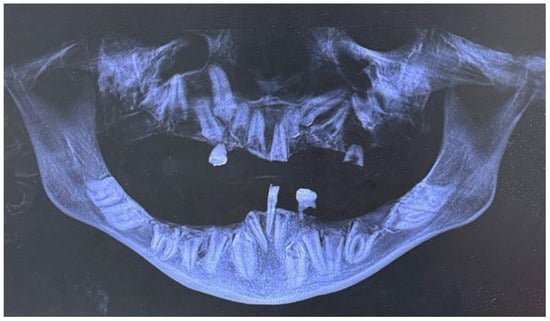

Extraoral examination revealed facial asymmetry, a dolichofacial growth pattern, and a concave facial profile (Figure 1a,b). As for the patient’s dental situation, intraoral clinical evaluation showed the presence of teeth 3.1, 5.3, and 7.4, along with a root remnant likely corresponding to 2.5 (Figure 2a,b,c,d,e). She showed a skeletal class III relationship due to the absence of erupted teeth. The patient’s mandible appeared prognathic, while the maxilla was severely hypoplastic [19,20]. The orthopantomography (OPG) revealed the presence of multiple impacted teeth, most of which exhibited abnormal morphology and incomplete development (Figure 3) [21]. The OPG was acquired using standard panoramic settings (66–70 kVp, 8–10 mA, exposure time 12–14 s) to obtain a comprehensive overview of dental development, impactions, and bone morphology. CBCT imaging was performed using a small-to-medium field of view (FOV 8 × 8 cm), 90 kVp, 5 mA, and a voxel size of 0.2 mm, allowing detailed assessment of tooth morphology, root development, and three-dimensional spatial relationships essential for treatment planning. Cone-beam computed tomography (CBCT) confirmed the findings and aided in treatment planning (Figure 4) [22]. Clinical photographs and radiographic records were collected, and the patient was enrolled in a multidisciplinary dental and prosthetic rehabilitation program.

Figure 3. Orthopantomography (OPG). The OPG image confirms multiple impacted permanent teeth throughout both the upper and lower arches, with abnormal morphology and incomplete root development of the retained elements.

3. Results

Despite the patient’s age of 24 years, the observed clinical features were consistent with a diagnosis of Infantile Refsum Disease (IRD). Clinically, the patient presented with a severe state of near-complete edentulism, with only the permanent incisor 3.1 and the retained deciduous teeth 5.3 and 7.4 present in the oral cavity. Skeletally, the patient exhibited a Class III relationship characterized by severe maxillary hypoplasia and mandibular prognathism (Figure 1a,b). The distinguishing aspect of the present case was the patient’s longevity and the unique radiographic finding of multiple impacted permanent teeth (including elements 1.1–1.8, 2.1–2.4, 2.6–2.8, 3.2–3.8, and 4.2–4.8) and near-complete edentulism—a combination not previously reported in association with this disorder (Figure 5). The patient was referred to a multidisciplinary prosthetic rehabilitation program.

Figure 5. The Orthopantomography (OPG) image displays the patient’s dentition with numerical labeling of the dental elements, using the standard FDI (Fédération Dentaire Internationale) system.

3.2. Radiographic Findings

Orthopantomography (OPG) and Cone-Beam Computed Tomography (CBCT) confirmed significant dental anomalies. The majority of the permanent dentition was impacted, including all permanent elements from 1.1 to 1.8, 2.1 to 2.4 and 2.8 (maxilla), 3.2 to 3.8, and 4.2 to 4.8 (mandible). Most of these impacted teeth exhibited abnormal morphology and incomplete development. Element 4.1 was absent due to prior extraction for advanced tooth decay at age 11. Such a severe pattern of dental impaction and tooth loss resulted in the observed near-complete edentulism, a finding that severely impaired oral function.